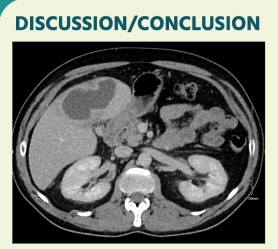

CT Abdomen/Pelvisshowed an 8.5cm liver abscess, predominantlylocated within segment5.Some mural thickening of the distal oesophaguswith periesophageal and coeliacaxis lymph nodeswas also noted.He wasfollowedupwithOGDwhichshowedahiatusherniaandgastritis.

Treatmentwas with IV antibiotics (piperacillin/tazobactam) for 6 weeks and CT guided drainage of the abscess. Thedrain wasremoved after 3 weeks.